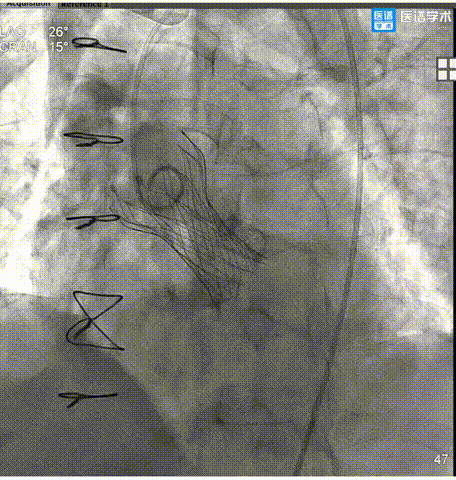

6.瓣膜释放至工作位后,造影评估示瓣膜植入较深,遂行完全回收重定位再释放。

7. 第二次释放后,经多投照角度评估,瓣膜仍存在植入过深情况,遂进行第二次完全回收重定位再释放。